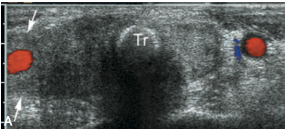

Label the image

A

Identify each structure

Describe its US appearance + location in relation to the thyroid

1. Strap muscles (anterior/ thin hypoechoic band)

2. Sternocleidomastoid m. (lateral/ oval hypoechoic)

3. Longus colli m.(posterolateral/ triangle)

4. Trachea (posterior midline/ air shadow)

5. Esophagus (posterior to left lobe/ target)

6. CCA (lateral)

7. IJV (lateral